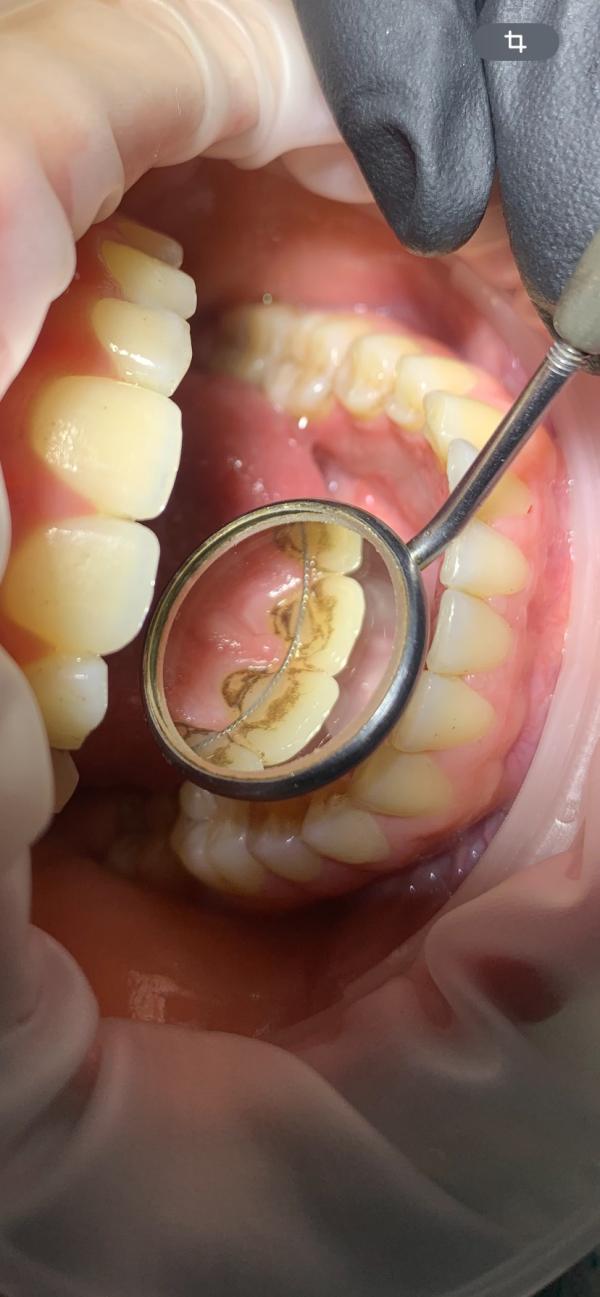

Профессиональная чистка Зубов 2500₽🦷✨🩵

Запись по номеру 89886486800💁🏻‍♀️📱